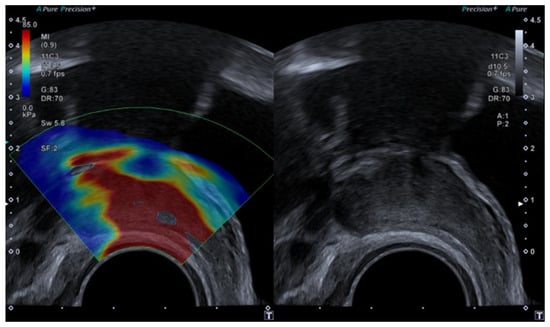

4.3. Elastography in Testicular Lesions